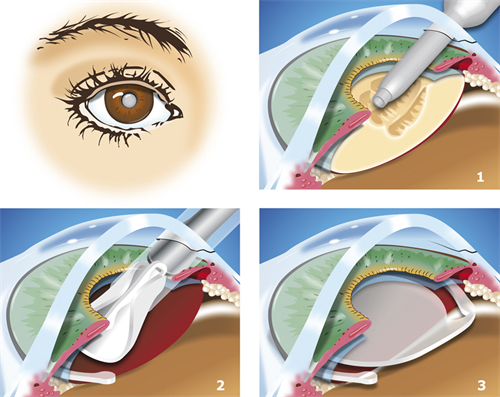

人工晶体置换需通过角膜切口将人工晶体植入眼内,若术中无菌操作不严或术后护理不当,细菌可能通过切口侵入眼内,引发眼内炎。

晶体移位:视觉稳定的“定时炸弹”

人工晶体依赖周边囊袋固定,若术中囊袋撕裂、术后剧烈运动或眼部受到外力撞击,晶体可能发生偏移或脱位。

患者会出现视力模糊、重影,甚至完全丧失视力。一位高度近视患者术后因搬运重物导致晶体脱位,需紧急手术重新固定晶体。

人工晶体度数需根据术前角膜曲率、眼轴长度等参数计算,但个体差异可能导致计算偏差。

若晶体度数与实际需求不匹配,患者术后仍需佩戴眼镜矫正视力。例如,一位白内障患者术后因晶体度数选择失误,看远清晰但看近模糊,需额外配戴老花镜。